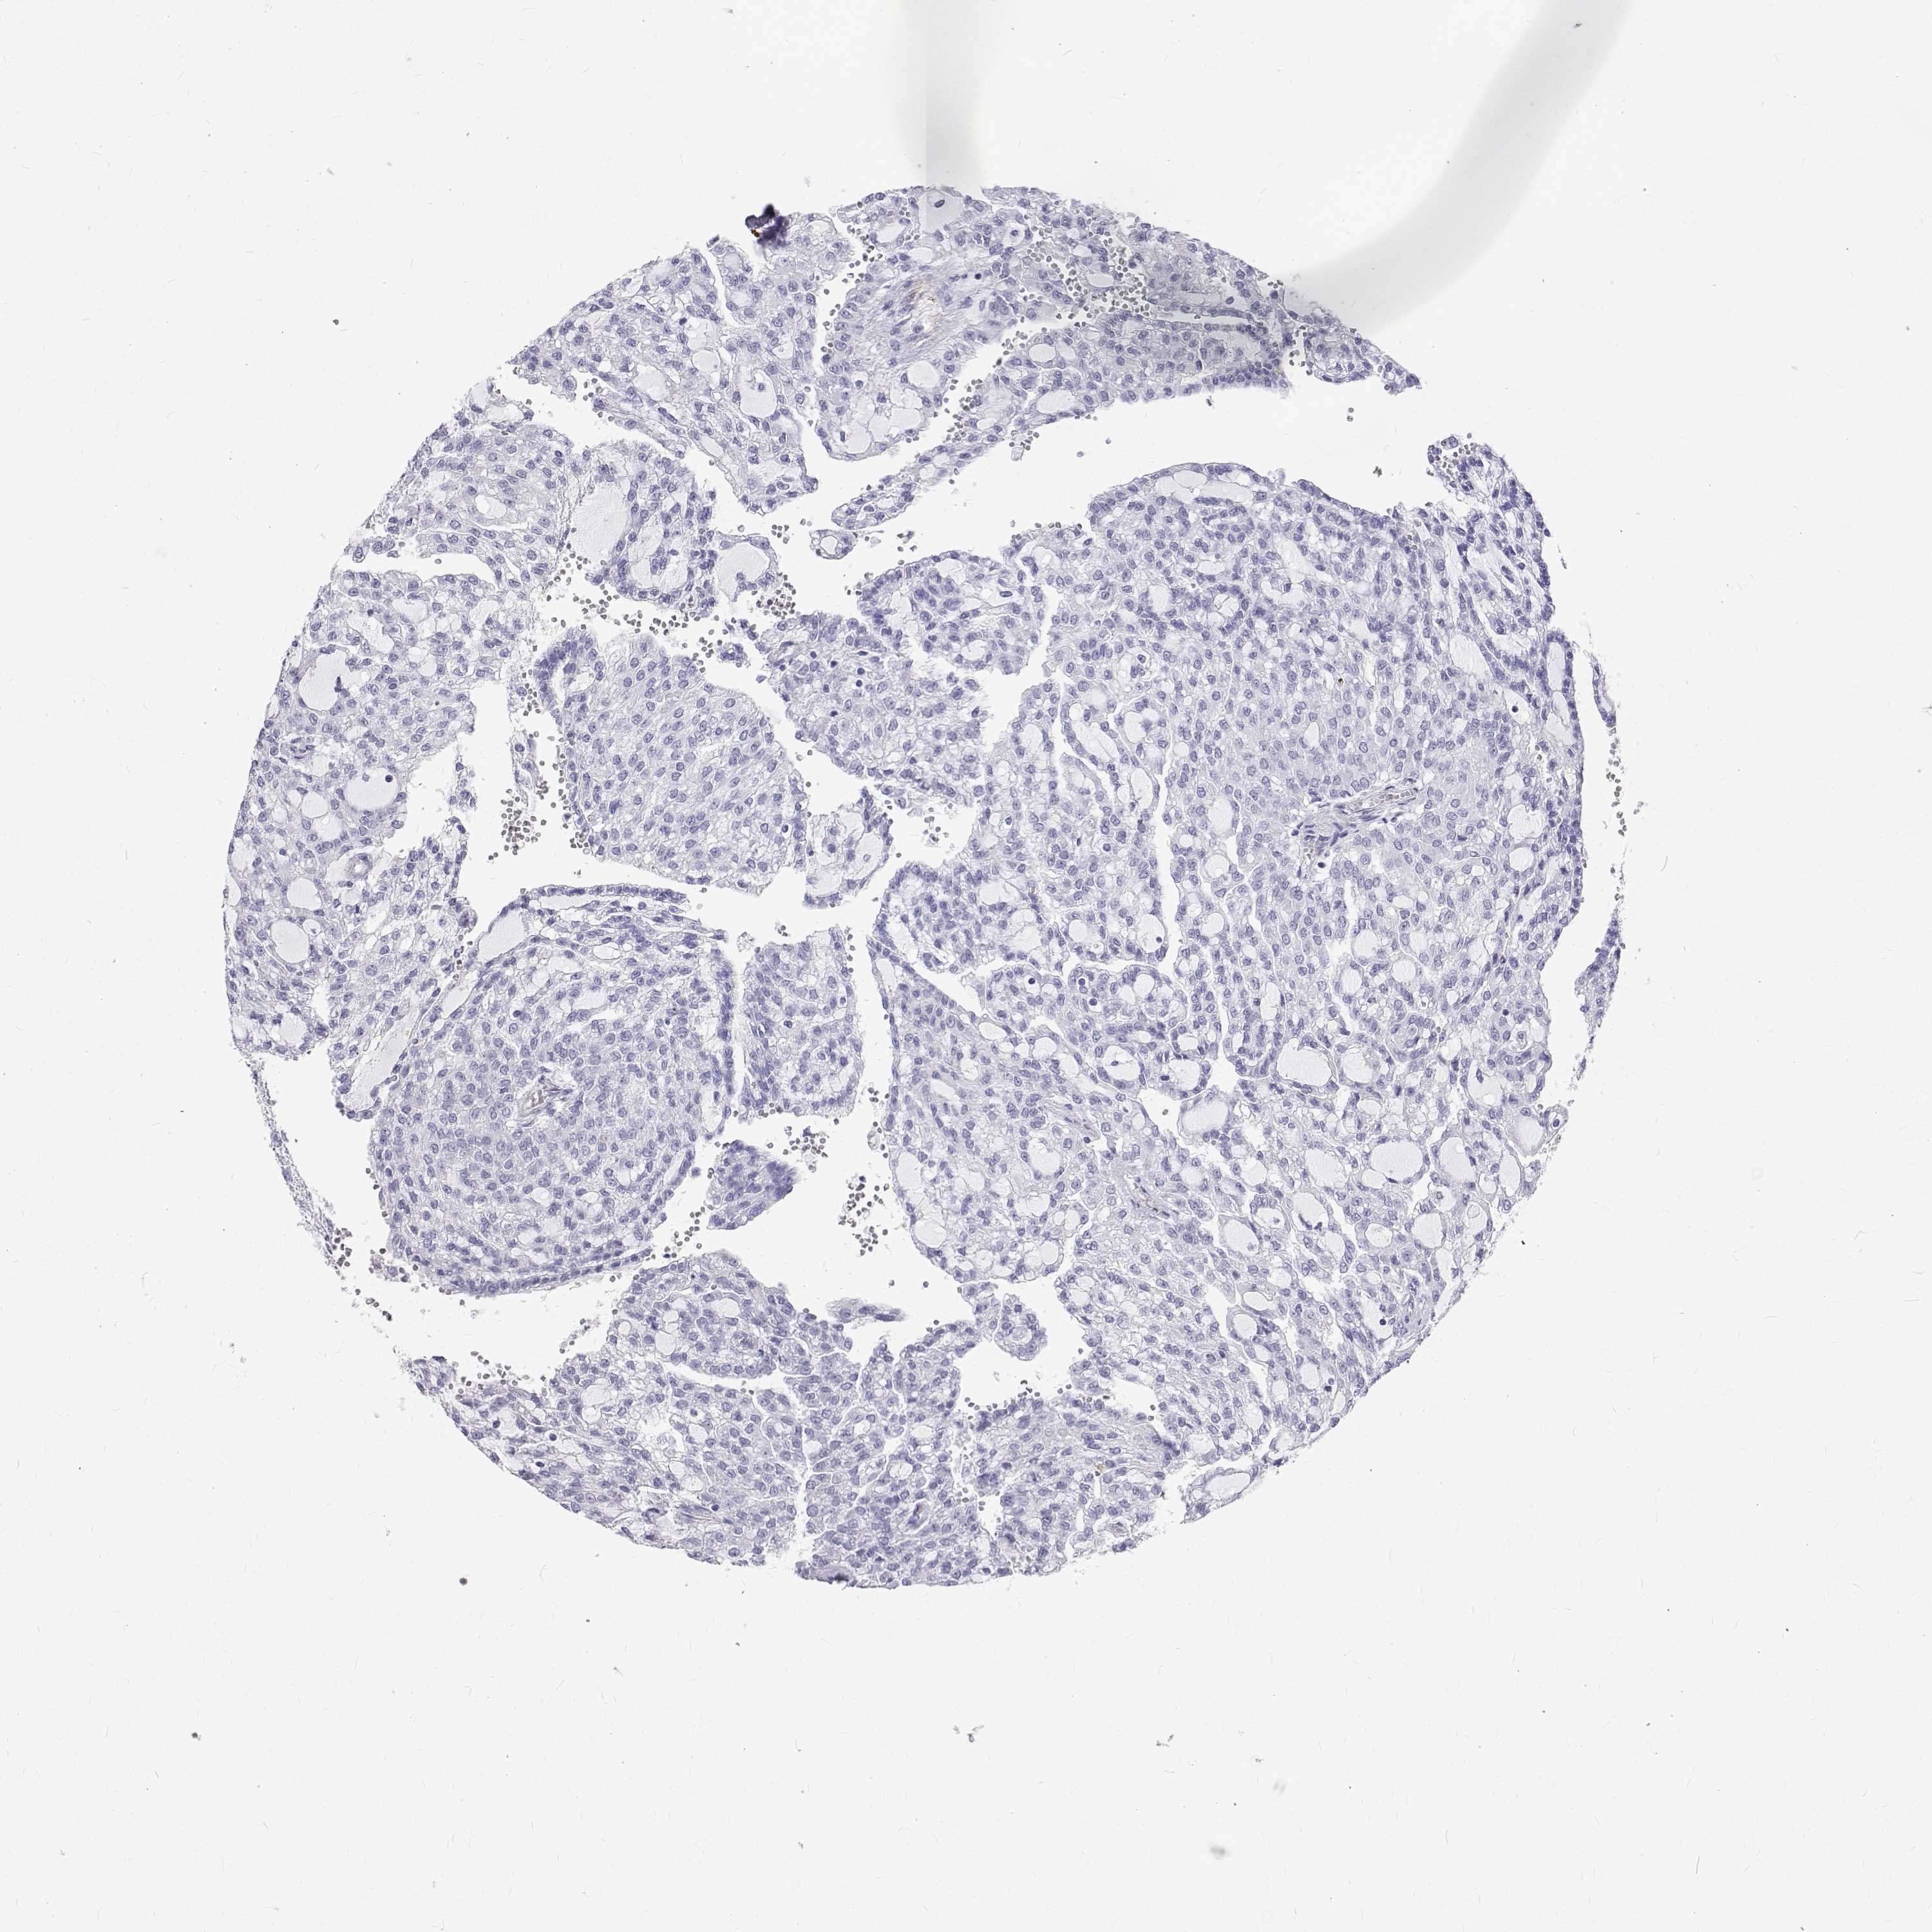

KIDNEY RENAL PAPILLARY CELL CARCINOMA (TCGA) - Interactive survival scatter ploti

The Survival Scatter plot shows the clinical status (i.e. dead or alive) for all individuals in the patient cohort, based on the same data that underlies the corresponding Kaplan-Meier plots. Patients that are alive at last time for follow-up are shown in blue and patients who have died during the study are shown in red.

The x-axis shows the expression levels (FPKM) of the investigated gene in the tumor tissue at the time of diagnosis. The y-axis shows the follow-up time after diagnosis (years). Both axes are complimented with kernel density curves demonstrating the data density over the axes. The top density plot shows the expression levels (FPKM) distribution among dead (red) and alive patients (blue). The right density plot shows the data density of the survived years of dead patients with high and low expression levels respectively, stratified using the cutoff indicated by the vertical dashed line through the Survival Scatter plot. This cutoff is automatically defined based on the FPKM cutoff that minimizes the p-score. The cutoff can be changed by dragging the vertical line or by entering a cutoff value in the square labeled "Current cut-off".

Under the Survival Scatter plot the p-score landscape (black curve; left axis) is shown together with dead median separation (red curve; right axis). Dead median separation is the difference in median mRNA expression between patients who have died with high and low expression, respectively. It is calculated as follows: median FPKM expression of dead patients with high expression - median FPKM expression of dead patients with low expression. This is intended to aid the user in visually exploring custom cutoffs and the associated p-scores and dead median separation.

Individual patient data is displayed and can be filtered by clicking on one or more of the category buttons on the top of the page. Categories describing expression level and patient information include: high, low, alive, dead, female, male and tumor stages. The scale of the x-axis can be toggled between linear and log-scale by clicking on the "x log" button. Mouse-over function shows TCGA ID, patient information and mRNA expression (FPKM) for each patient.

& Survival analysisi

Kaplan-Meier plots summarize results from analysis of correlation between mRNA expression level and patient survival. Patients were divided based on level of expression into one of the two groups "low" (under cut off) or "high" (over cut off). X-axis shows time for survival (years) and y-axis shows the probability of survival, where 1.0 corresponds to 100 percent.

Survival analysis data not available.

TCGA RNA samplesi

RNA-seq data is reported as average FPKM (number Fragments Per Kilobase of exon per Million reads), generated by the The Cancer Genome Atlas (TCGA) .

Normal distribution across the dataset is visualized with box plots, shown as median and 25th and 75th percentiles. Points are displayed as outliers if they are above or below 1.5 times the interquartile range. FPKM values of the individual samples are presented next to the box plot.

Average pTPM 0.0

Number of samples 282